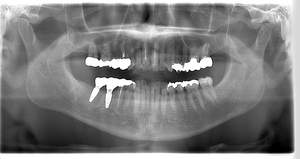

インプラント治療の症例1

レントゲン写真

- 透過像

| 年齢 | 50代・男性 |

|---|---|

| 主訴 | 右下歯が疼く |

| 治療内容 | ・右下6番インプラント ※1:FGG(遊離歯肉移植術)とは、足りない歯ぐきを上顎から上皮を切り取り移植する外科手術 |

| 治療費 | 合計:902,000円(税込) ■内訳 |

| 治療期間 | 9ヵ月 |

| 治療方針 | 右下の当該歯は歯根破折により保存不可能と診断しました。歯周疾患も伴っていたため抜歯後に骨吸収※1が大きく起こることが予測できました。チタンメッシュ併用骨再生誘導法(GBR※2)を選択しインプラント埋入と同時に行い自然な歯槽骨のラインを再現しました。またGBRを行う際にインプラント辺縁の付着歯肉の減少が起こる為、遊離歯肉移植術(FGG※3)を行い清掃性を考慮した形態に仕上げました。 ■治療方針の解説 治療した右下の歯をレントゲンで撮影したところ根本の部分に黒く写る箇所があり「根尖性慢性周囲炎※1」と診断。また歯周病も進行していました。 ※1 骨吸収・・・歯槽骨という歯を支える骨がなくなっていくこと |

| 担当者所見 | 主訴の右下だけでなく歯茎の腫れ、発赤があり不良補綴や不良充填など他にも治療箇所が多数ありました。プラークコントロールが不良であった為まずはブラッシング指導を行いセルフケアの重要性を理解していただくところからスタートしました。 右下6番の歯はインプラント治療を行なった結果審美的にも機能的にも患者様の満足を得ることができました。骨造成と歯肉移植も行なった為インプラントを支える十分な歯周組織の獲得ができたと思っております。 |